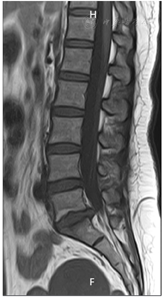

辅助检查:2022年07月20日腰椎MRI示L5/S1椎间盘变性并右后方脱出,S1右侧神经根中心区受压(图1,图2,图3,图4)。

患者慢性病程,反复发作并逐渐加重,以腰腿痛为主诉,无间歇性跛行,无夜间疼痛加重,无潮热盗汗,无二便障碍,完善腰椎MRI提示L5/S1椎间盘变性并右后方脱出、S1右侧神经根中心区受压,诊断LDH并坐骨神经痛。